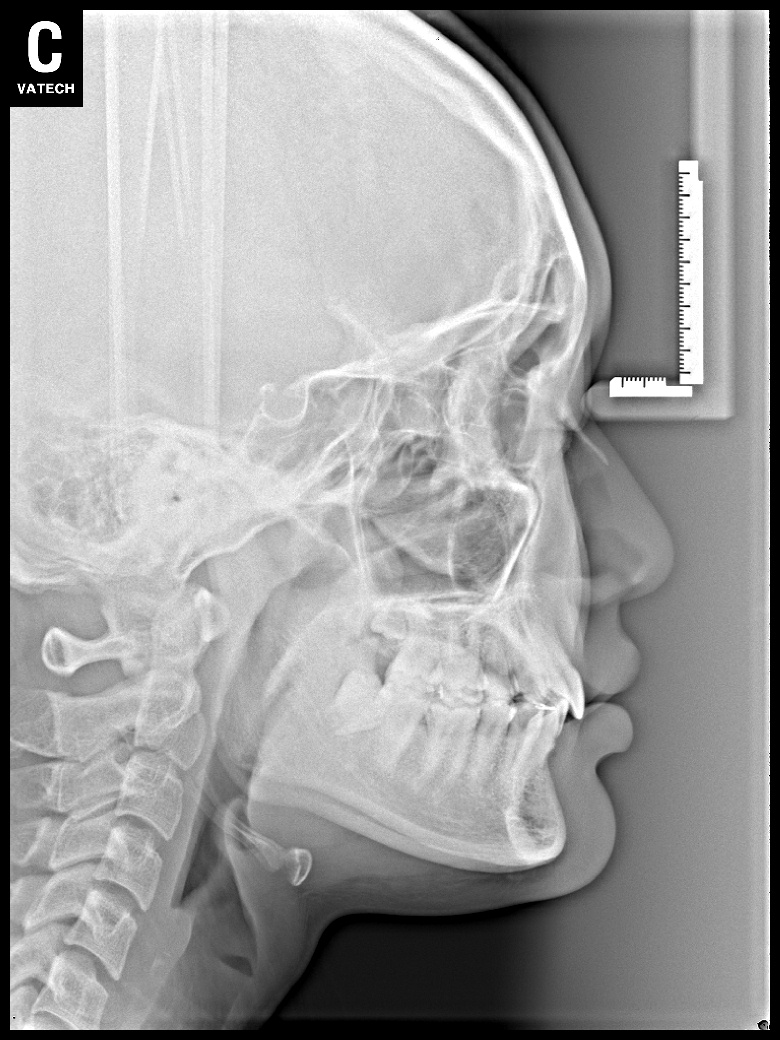

치료 전 사진입니다.